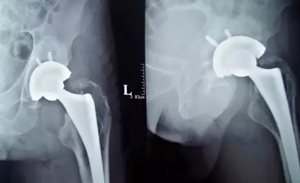

来到我院后,便立即对徐先生进行腰椎、骨盆DR检查。诊断为:左股骨头缺血性坏死,双髋骨性关节炎,强直性脊柱炎,左侧股骨相隆陈旧性骨折,肝囊肿左肾囊肿,左肾结石。入院后,结合病人的病史为徐先生制定了详细的手术方案、手术时间。

患者于8月13日进行 “左侧人工髋关节置换术”,由胡玉华院长,李龙付副主任为患者手术,1小时30分钟后手术顺利结束,病人被推入病房。经过一段时间的精心治疗和护理,徐先生的恢复得很好,已经能够自己下地行走。

人工髋关节置换术的治疗效果经过三十多年的临床实践,已经得到充分的肯定并已经发展成为一种可靠的治疗手段。人工关节置换术主要目的是缓解关节疼痛、矫正畸形、恢复和改善关节的运动功能。术后通过康复训练,患者基本上都可以恢复到正常人的活动水平。